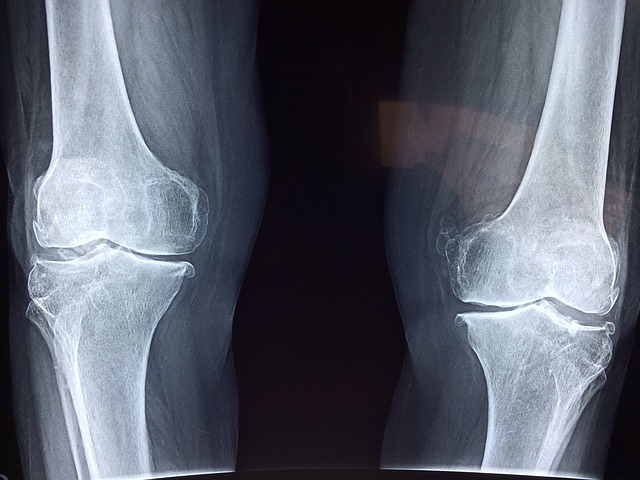

약해지고 부서지기 쉬운 뼈를 특징으로 하는 골다공증은 종종 골밀도 손실로 인해 발생하며, 이로 인해 개인이 골절에 더 취약해집니다. 골다공증의 원인을 이해하는 것은 예방과 효과적인 관리 모두에 매우 중요합니다. 노화는 주요 요인으로, 골량은 성인 초기에 최고조에 달하고 그 이후에는 점차 감소합니다. 특히 폐경기 이후 여성은 골밀도에 영향을 미치는 호르몬 변화로 인해 위험이 증가합니다.

골다공증의 중증도는 종종 골밀도(BMD) 검사를 통해 평가되며, BMD가 낮을수록 골절 위험이 증가함을 나타냅니다. 골다공증의 다양한 원인과 심각도 요인을 이해하는 것은 뼈 건강에 대한 적극적인 접근 방식을 구축하는 첫 번째 단계입니다.